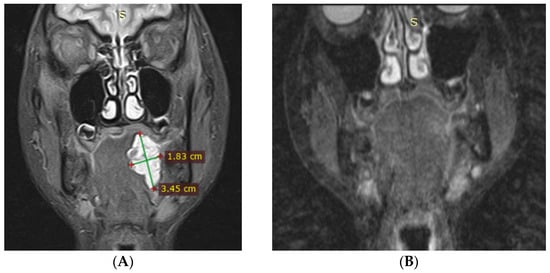

3.1. Magnetic Resonance Imaging (MRI) Findings